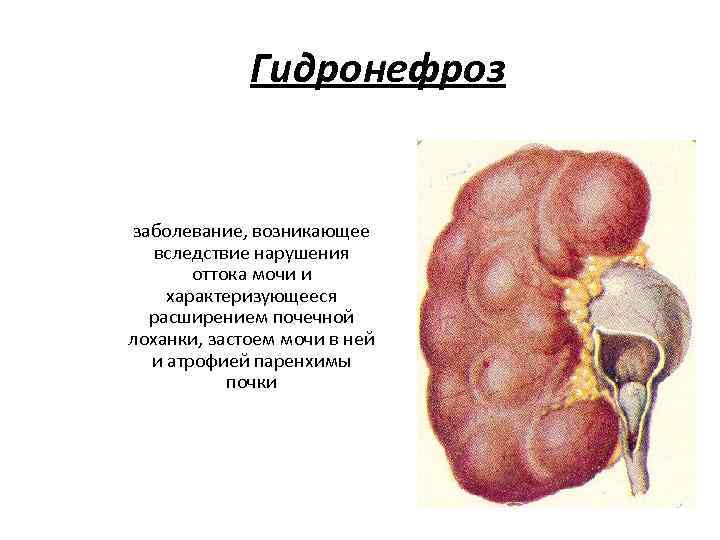

Интраренальная лоханка: рентгеновские снимки и примеры